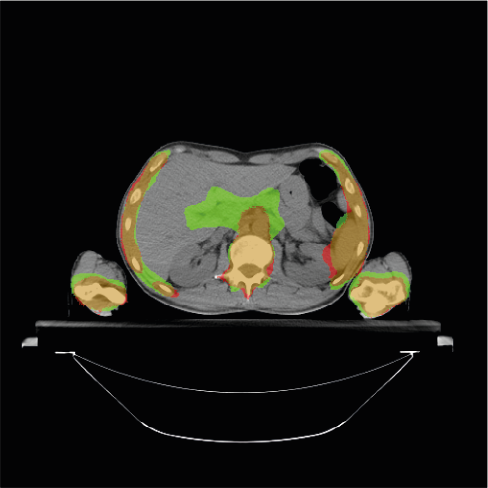

To further understand the areas where the models do not accurately segment the PTV, we provide some visual examples of the poor segmentations Figure 4. The first row of the Figure 4 shows four examples of slices poorly segmented by the BCEL model. The first slice (Figure 4a) corresponds to the head and neck area. The segmentation error in the left and right areas of the head (i.e., the green areas) may be due to conservative segmentation of the second level of neck lymph nodes in the ground truth. The standard reference point for segmenting these lymph nodes might be a slightly higher slice, but the radiation oncologist likely included the target on this slice due to the large CT thickness of 5 mm. The second slice (Figure 4b) shows an absence of hepatic portal lymph nodes. This area is subject to high anatomical variability, and due to the lack of contouring guidelines [38] in the early years of data acquisition, this area was often omitted by the radiation oncologist. In the third slice (Figure 4c), the absence of the pre-sacral lymph nodes (anterior to the sacrum) is evident. Moreover, the predicted segmentation of the external iliac lymph nodes is inaccurate. This target area is defined by adding a margin to the iliac vessels. In the fourth slice (Figure 4d), representing the legs area, the prediction fails to segment the inguinal lymph nodes, likely because these are frequently omitted by physicians. The second row of the Figure 4 shows the same slices overlayed with the predictions of the DL model. Notably, the segmentation errors of the DL model closely resemble those of the BCEL one, previously discussed. Please notice that the segmentation mistakes of DL model are very similar to the ones of the BCEL model, previously discussed. Nevertheless, a higher propensity for false negatives is discernible in the DL model’s segmentations, evidenced by the larger green regions surrounding the bones in Figure 4h and within the iliac lymph node area in Figure 4g.